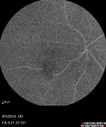

Macroaneurysm FA620 viewsMacroaneurysm with Subretinal Hemorrhage and ME in OS of an Elderly Female

Macroaneurysm FP1068 viewsMacroaneurysm with Subretinal Hemorrhage and ME in OS of an Elderly Female